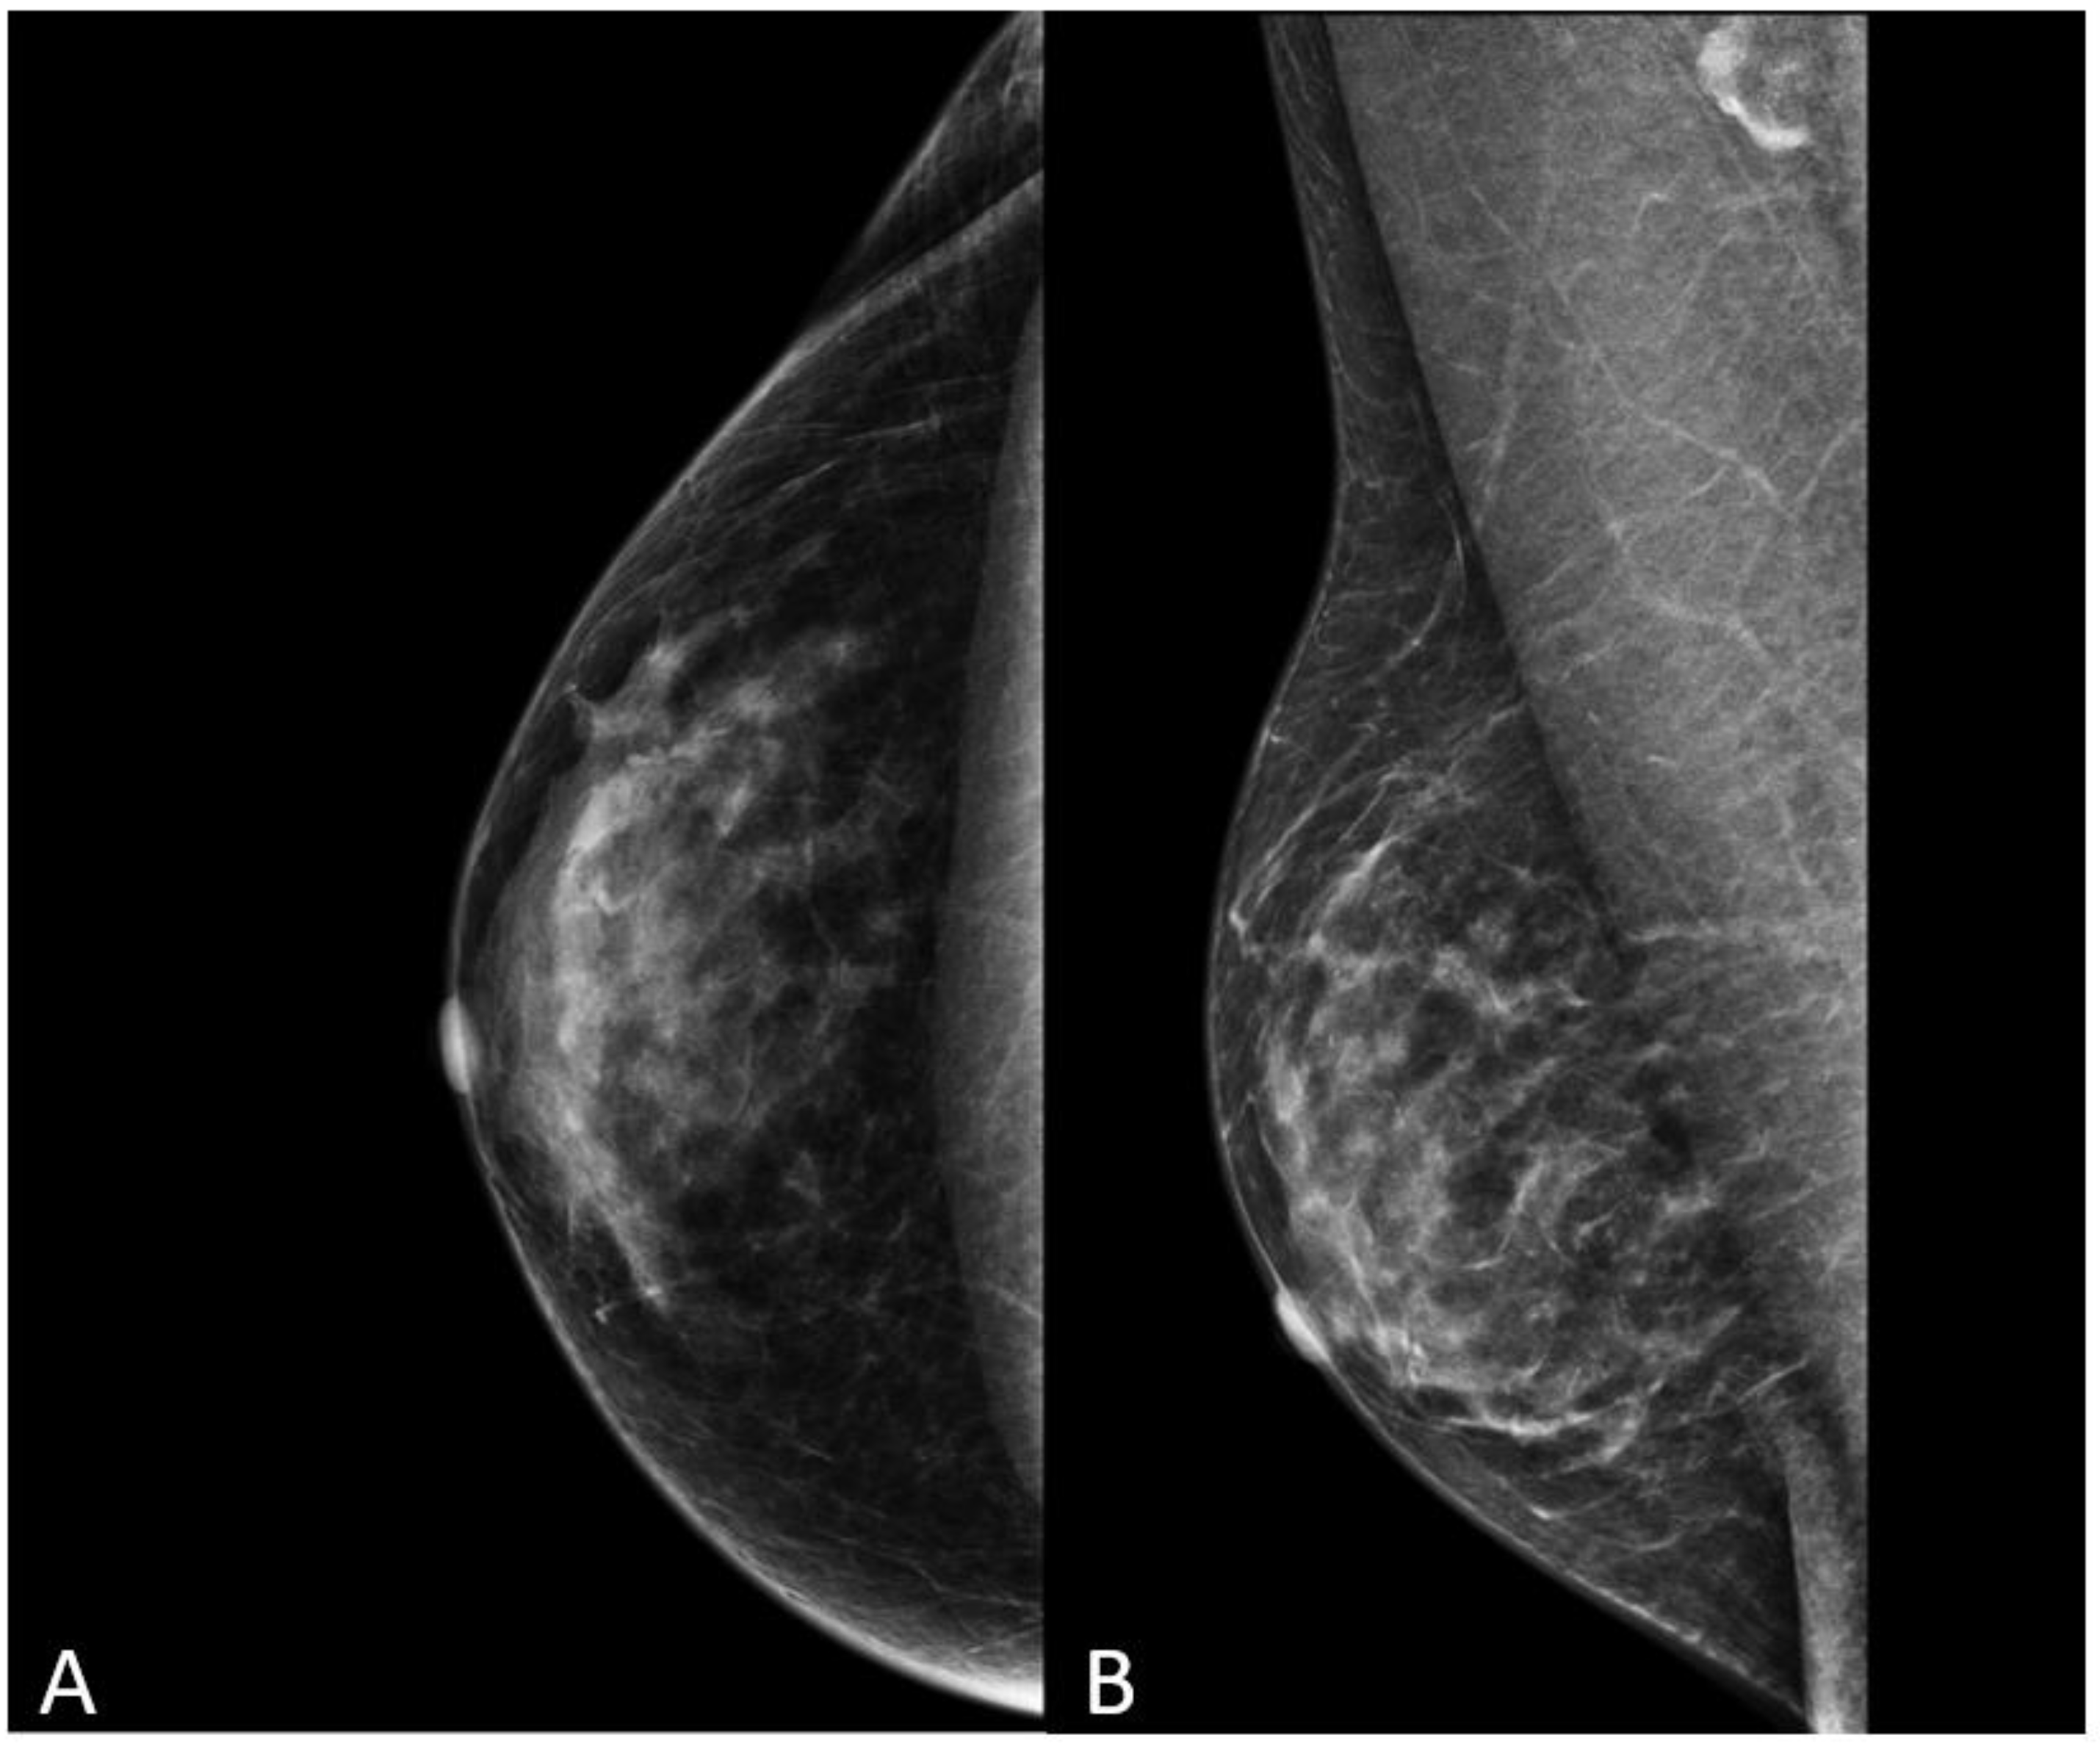

The most common histological subtype of primary malignant breast lesions in men is invasive ductal carcinoma (IDC) [27,28], shown in Figure 7.

Figure 7.

A 60-year-old man with gynecomastia presenting a retroareolar lump on the right breast with nipple retraction and without nipple discharge. Histological examination revealed an invasive ductal carcinoma (ER + 90%, PR + 60%, HER2 score 1+). Ultrasound examination (A) shows a hypoechoic irregular mass (white arrow) in the retroareolar region, with lobulated margins. A mammography (B) shows an irregular hyperdense retroareolar mass with lobulated margins (red circle).

IDC typically originates from the terminal duct–lobular unit [28,29]. Clinical features include a palpable unilateral retroareolar mass with nipple retraction and skin thickening [28,29]. Around 25% of cases may present with bloody nipple discharge [28]. IDC can be associated with ductal in situ components in up to 50% of cases [30]. Mammographically, IDC appears as a retroareolar irregular high-density mass with spiculated or micro-lobulated margins [30,31]. Unlike in women, IDC in men is rarely associated with microcalcifications due to the involution of the ductal system caused by the absence of estrogen and progesterone stimulation [28,29]. Ultrasonography reveals solid, hypoechoic, and irregular masses with margins ranging from microlobulated to spiculated [32]. Papillary carcinoma (PC) is the second most common invasive subtype of MBC and has a higher incidence in men compared to women [33]. PC is characterized by neoplastic proliferation of cells with fibrovascular stalks lacking an intact myoepithelial cell layer [34]. It typically presents with bloody nipple discharge and occurs in the subareolar region. Mammographically, PC may exhibit well-circumscribed or spiculated margins, while ultrasound imaging may reveal a dilated duct or cyst, often appearing as a complex cyst with solid papillary projections along the cyst wall [35,36] (Figure 8).